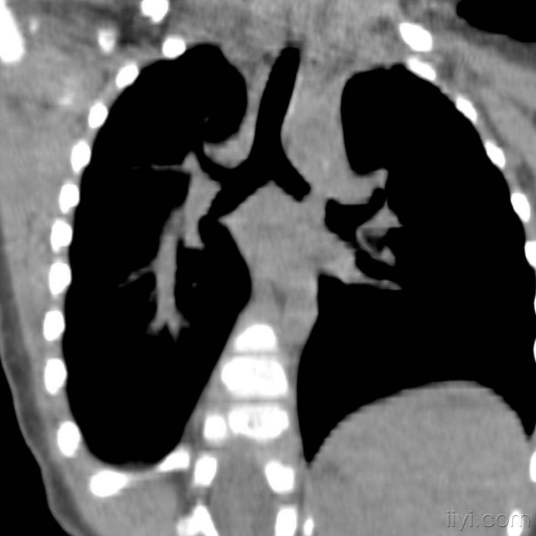

异物进入、停留或嵌顿于气管或支气管内的状态。多发生于5岁以下的儿童。常因儿童牙齿发育不完善、进食时哭闹或嬉笑,或因全身麻醉、昏迷病人将呕吐物或假牙等吸入所致。因右侧支气管管径较粗且陡直,故而异物常落入该侧支气管内;若两侧支气管受堵则可引起窒息死亡。